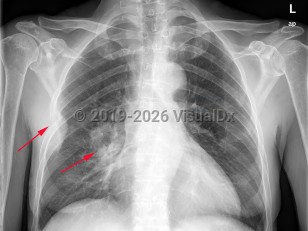

EVALI